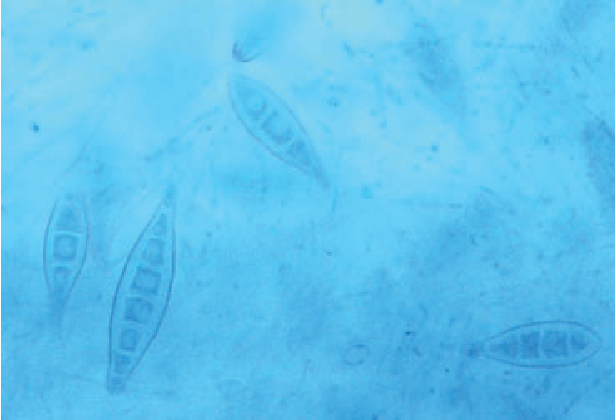

Microsporum Canis Pictures